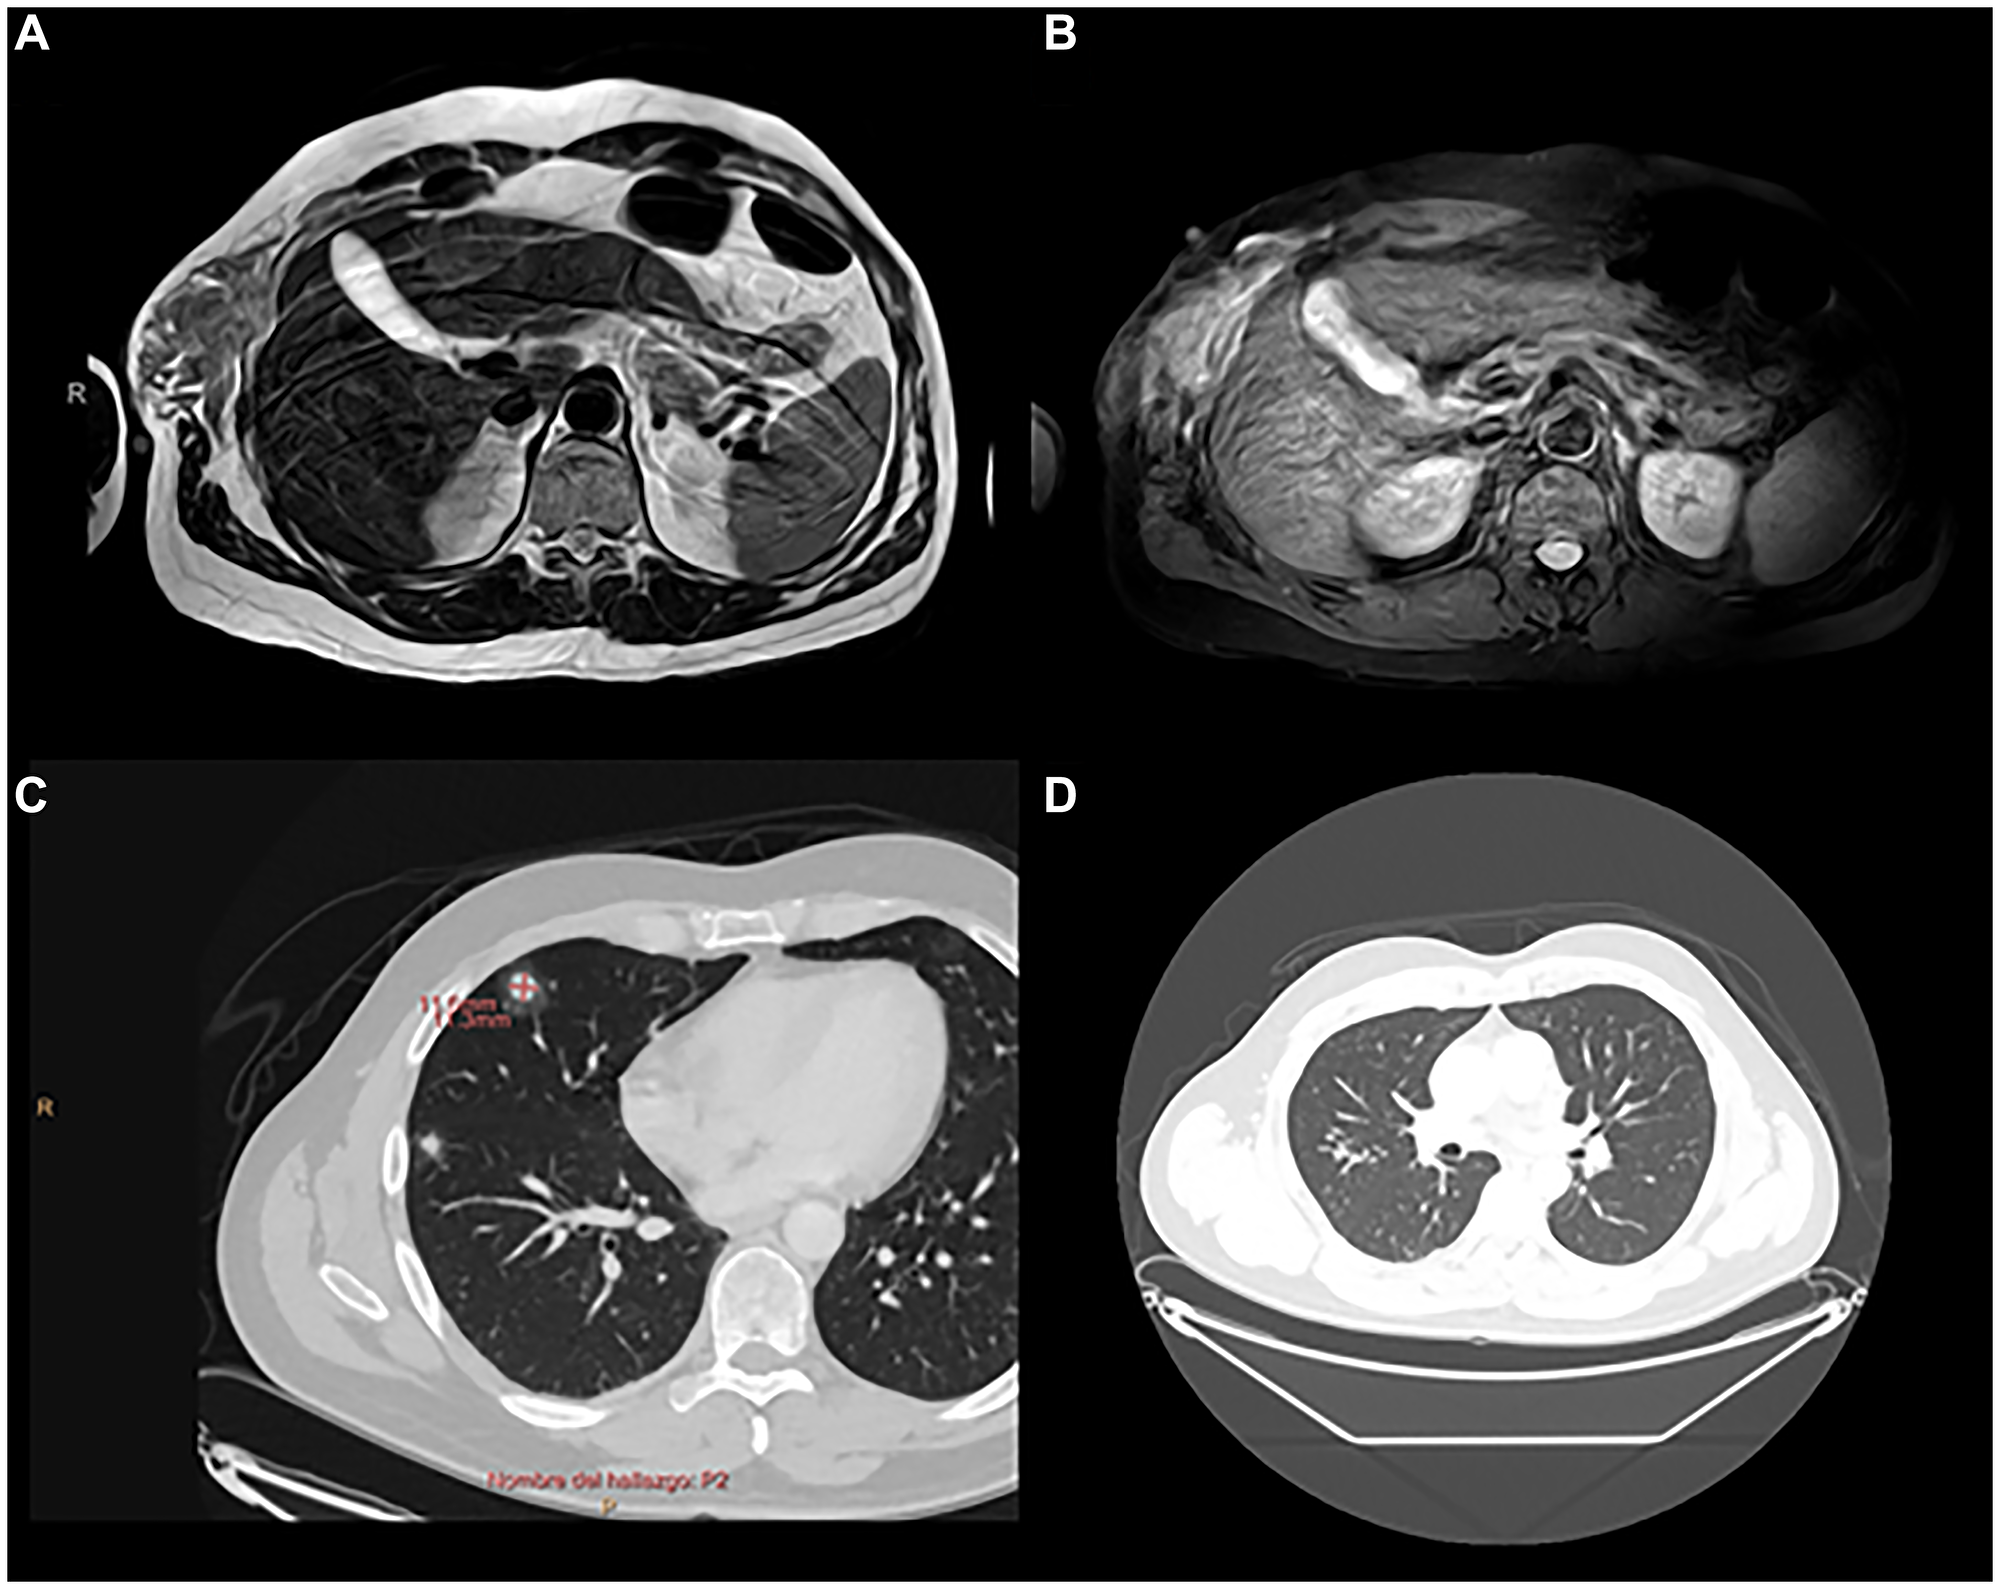

25 years later, in April 2021, due to persistence of pain and the appearance of a palpable mass at that level, magnetic resonance imaging (MRI) was performed, showing a tumor located in the right chest wall, extending towards the intercostal musculature and accompanied by two small adjacent subcutaneous tumors (Figure 1).

Figure 1: Chest MRI 04/22/2021.

Soft tissue tumor (32 × 23 mm) on the right chest wall, located deep to the superficial fascia, in relation to the serratus muscle and extending towards the intercostal musculature, superficial to the costal arches. Small subcutaneous tumors, the largest measuring 8 mm in diameter, on the thoracic and abdominal wall.